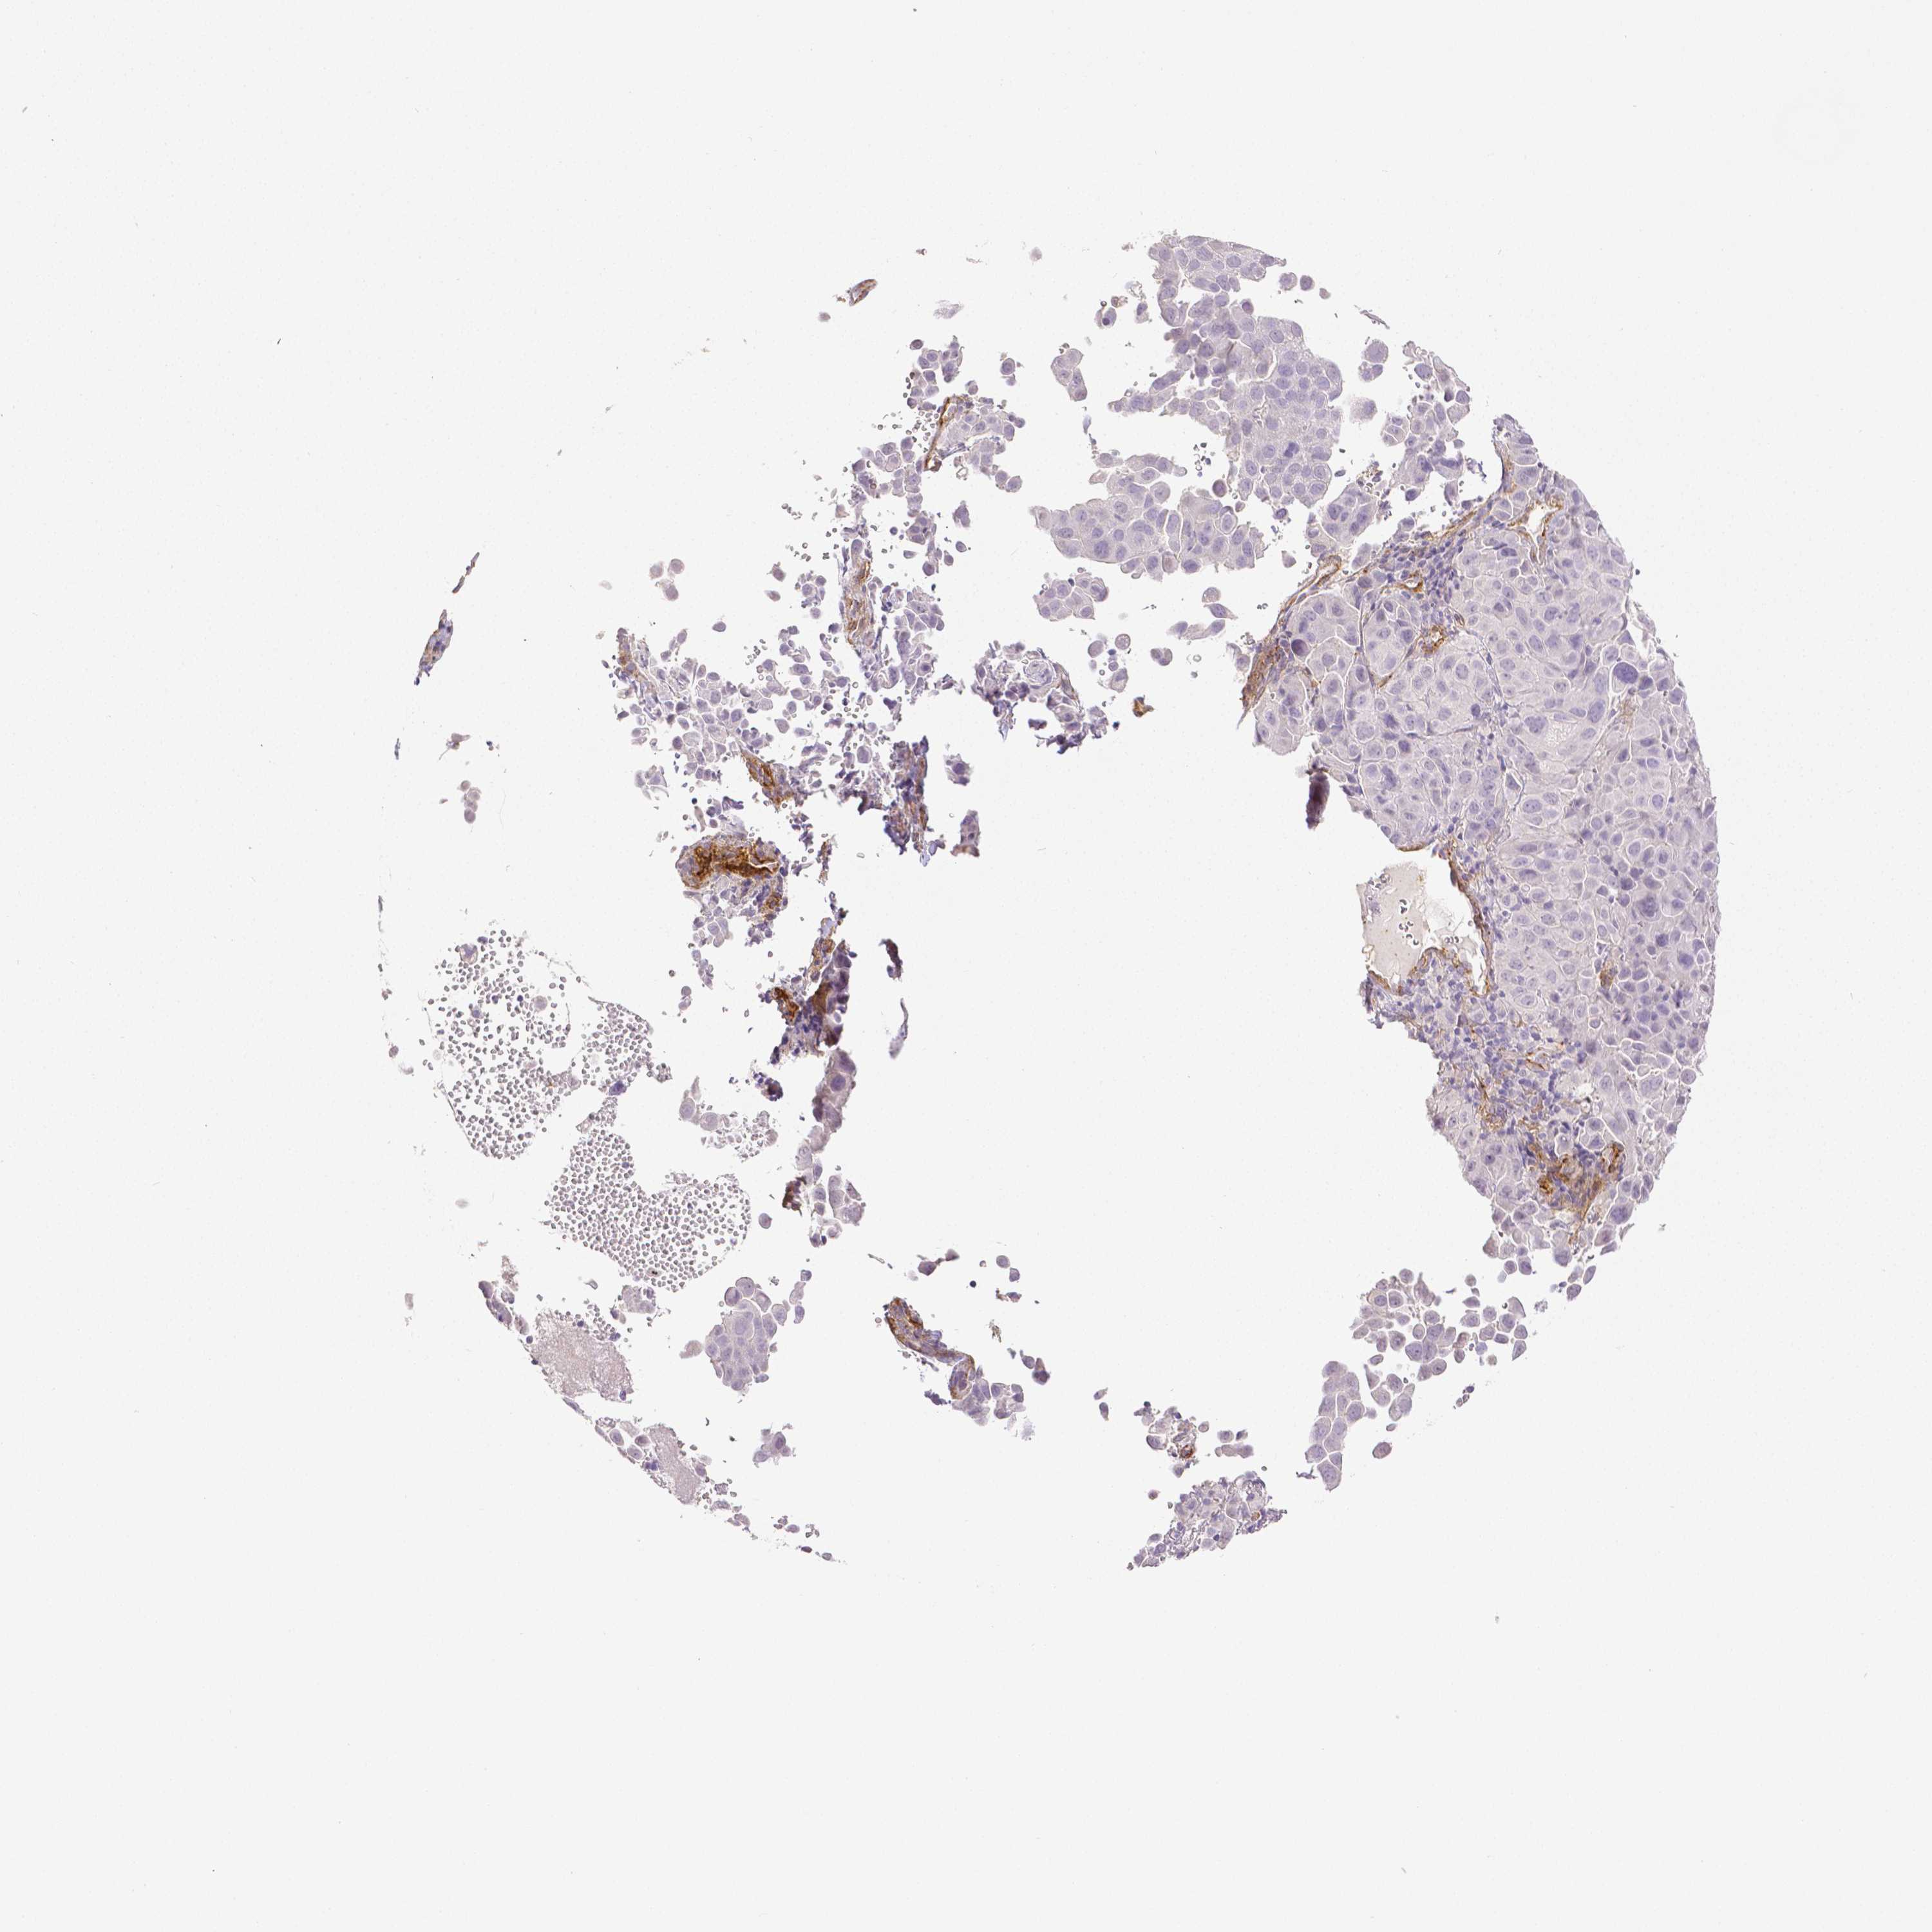

CERVICAL CANCER - Protein expressioni

A mouse-over function shows sample information and annotation data. Click on an image to view it in a full screen mode. Samples can be filtered based on level of antibody staining by selecting one or several of the following categories: high, medium, low and not detected. The assay and annotation is described here.

Note that samples used for immunohistochemistry by the Human Protein Atlas do not correspond to samples in the TCGA dataset.

Antibody stainingi

Antibody staining in the annotated cell types in the current human tissue is reported as not detected, low, medium, or high, based on conventional immunohistochemistry profiling in selected tissues. This score is based on the combination of the staining intensity and fraction of stained cells.

Each image is clickable and will lead to virtual microscopy that enables deeper exploration of all samples and also displays staining intensity scores, fraction scores and subcellular localization as well as patient and tissue information for each sample.

Antibody HPA003733

Antibody CAB068243

Antibody CAB068244

Squamous cell carcinoma, NOS

Adenocarcinoma, NOS